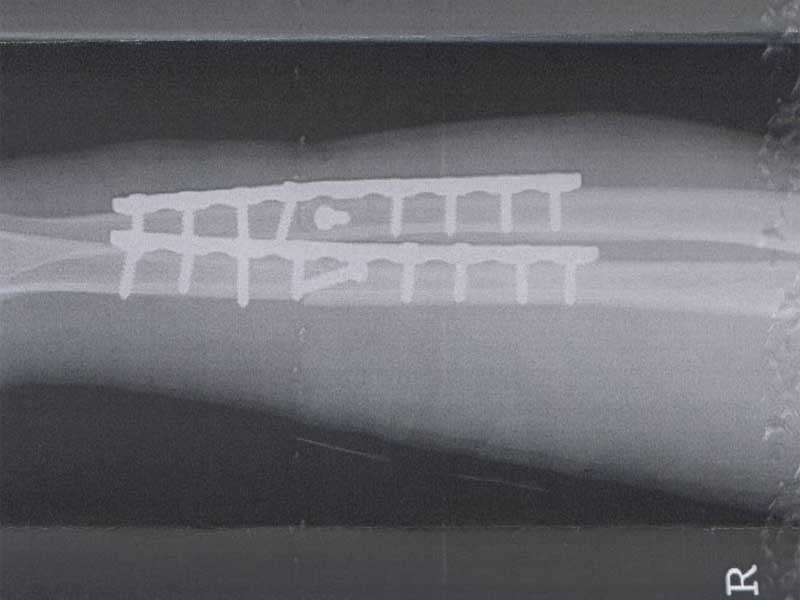

In gedenken An Dark's TDR leidet ist sie unter einem Laster gekommen der beim Abbiegen nicht auf gepasst hat.

Ergebnis: TDR=Totalschaden Dark-Rider=Arm gebrochen (2x9Loch-Platten und 18xSchrauben)